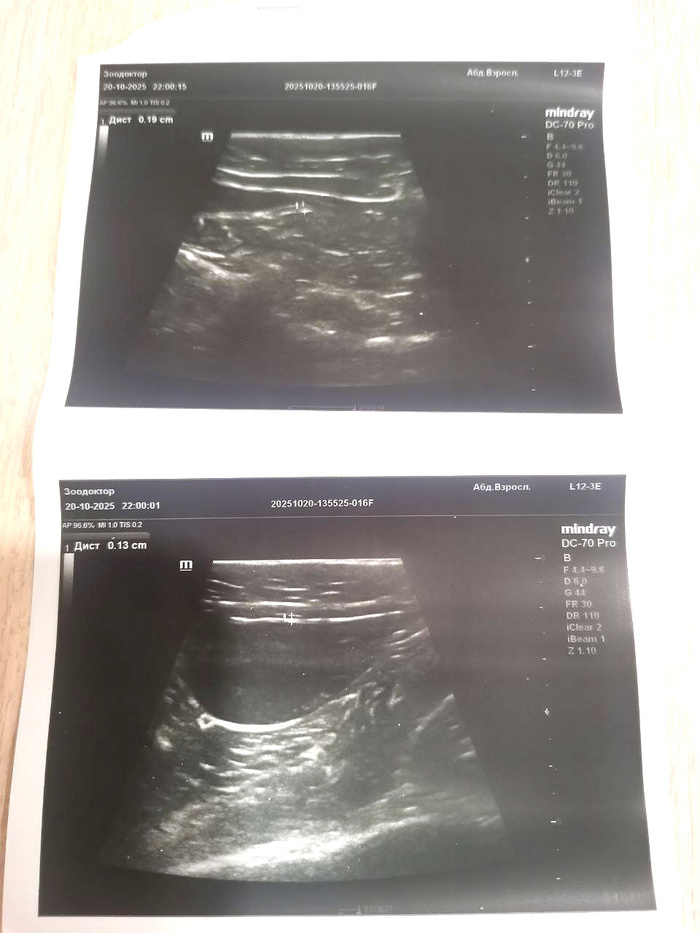

Записали Шанталика на прием в понедельник. Скорее всего, понадобится сделать УЗИ и сдать мочу на бак.посев.

Наша Катя свозила Шанталика в клинику 20 октября (4880р.). К счастью, ничего критичного на УЗИ не обнаружилось:

камней в мочевом пузыре нет. Взяли мочу на анализ методом цистоцентеза – результат приемлемый. Но есть песочек – судя по всему, именно он и тревожит Шаню, не дает сходить в туалетик.Был еще повторный онлайн-прием по результатам анализа (1800р.). Прописанные таблеточки Омник Окас выкуплены (312р.), они помогли. Но стоило их прекратить – как у Шанечки образовался новый затык. Т.ч. Катя полечит ими Шанталика еще.